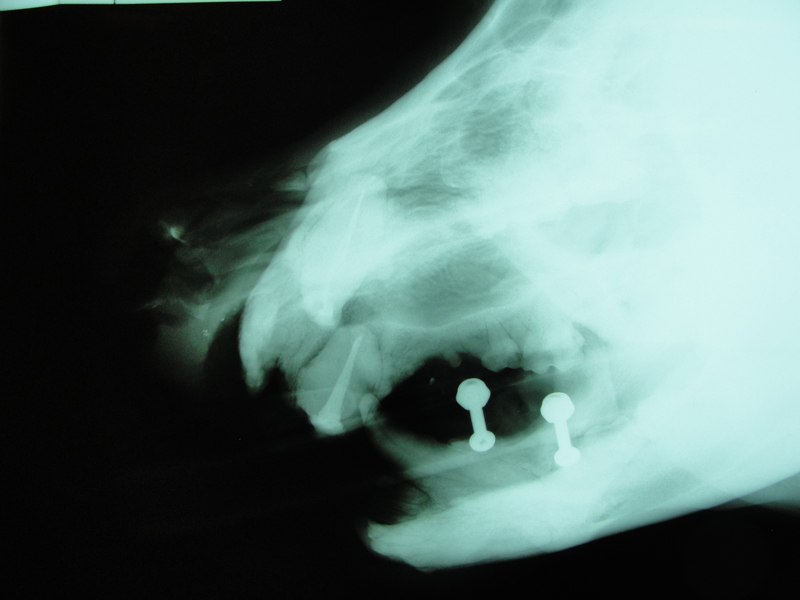

THE WEDGE®

Radiolucent Mouth Prop for Dogs and Cats

- Anatomically designed to provide secure, open mouth

- Use for anesthesia, radiography, oral surgery, and dentistry

- No moving parts, use if canines are absent

- Ultrasound, heat, or cold sterilize

- SMALL size for cats and smaller dogs, LARGE size for medium to large dogs

The WEDGE® is a one-piece, radiolucent mouth prop. The patented, anatomic design holds the carnivore mouth open during anesthesia by securely engaging the premolars and molars.

- Radiolucency facilitates clear open-mouth radiography.